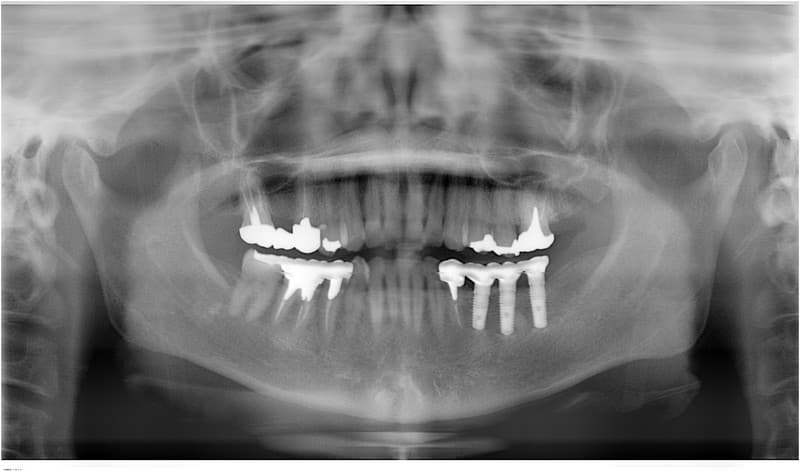

- 外科処置によって顎の骨にインプラントを埋め込みます。

- 3~6ヶ月後にインプラントに人工の歯を連結するためのパーツを取り付けます。

(小外科処置を伴います。)